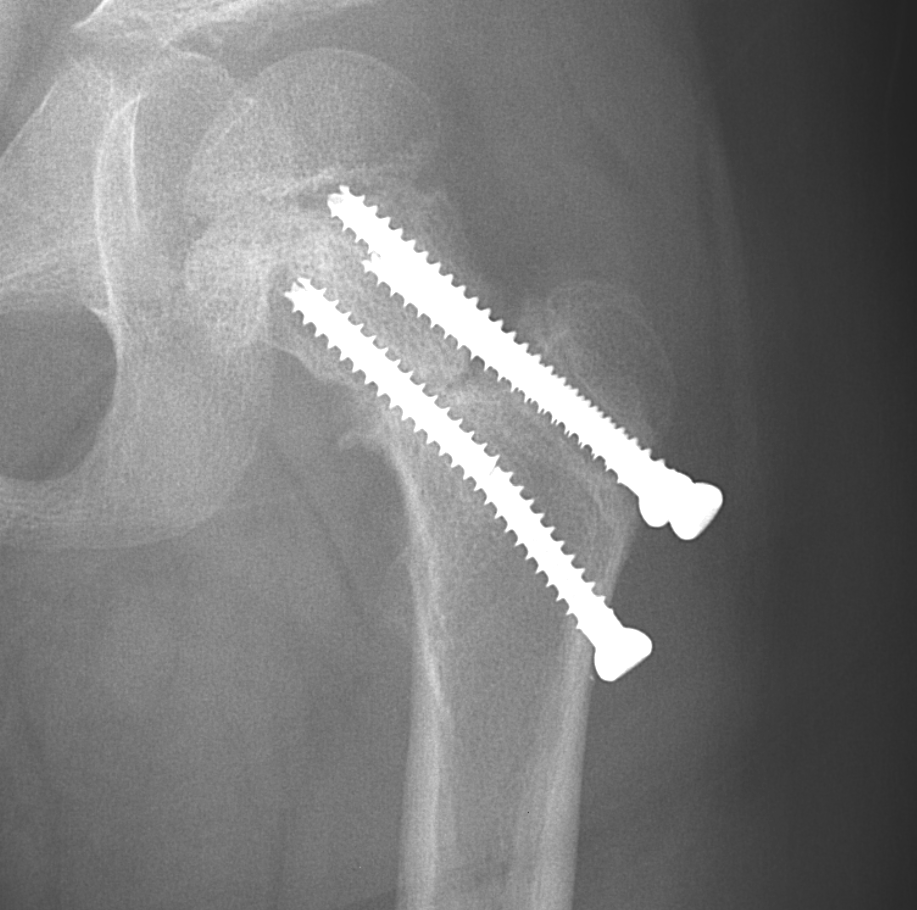

Info Images Findings Impression Reco/Acuity Case Images View Images / Launch Visage Case Notes History 2-month-old presents with decreased right arm movement, increased fussiness, and increased sleepiness for 2 days. Suspected non-accidental trauma. Exam Skeletal survey Prior Study none Dicom View Reference Material

Section 1 Submit Findings CB1550 Findings Skeletal Survey - Technique Check Skull AP/Lat Yes No Cervical and Thoracolumbar spine Yes No Chest X-Ray Yes No Ribs – Left/Right Oblique Yes No Abdominal X-Ray Yes No Pelvis with both hips Yes No Bilateral Humerus, Forearm, Hand Yes No Bilateral Femur, Tibia/fibula, feet Yes No Any additional lateral views of the extremities Yes No The exam is over or under penetrated. Yes No The exam may or may not be limited by overlying structures or soft tissues, body habitus, patient positioning, support devices, or motion. Yes No The area of concern is indicated by the patient, technologist, or care provider. Yes No The area of concern is included on the exam. Yes No Soft Tissues There is soft tissue swelling, indistinctness of fat/muscle planes, gas, or laceration in the area of clinical concern. Yes No There is an effusion, fat pad displacement, or fat fluid level. Yes No There is a radiodense or lucent foreign body. Yes No There are other densities, calcifications, post-surgical changes, or support devices in the soft tissues. Yes No Any support lines/tubes. Yes No Bone There is a break or interruption of the continuity of the cortical or cancellous bone. Yes No There is overriding of the trabeculae with apparent sclerosis. Yes No There is displacement of a fracture fragment. Yes No There is bowing of the bone in addition to the fracture at the apex of the bowed bone concerning for the greenstick. Yes No There is a spiral fracture of the leg concerning for toddler’s fracture. Yes No There is abnormal angulation or bulging of the cortical surface relative to the normal cortex which could be from a buckle or torus fracture. Yes No There is a displaced fragment which may be from avulsion by a tendon, ligament, or joint capsule or from a comminuted or other fracture. Yes No The stress trabeculae or other trabeculae of the cancellous bone are interrupted or otherwise abnormal. Yes No There is subperiosteal or endosteal reaction which could indicate a healing or subacute fracture or other abnormality. Yes No There is hard/soft callus formation. Yes No There is remodeling of the bone. Yes No There is a corner fracture or metaphyseal lesion that could be from nonaccidental trauma. Yes No There are multiple fractures of different ages. Yes No There are vertebral body/spinous process fractures. Yes No There are rib fractures. Location - posterior or lateral. Yes No There is scapular/sternal fracture. Yes No There are fractures of the digits. Yes No There are wormian bones. Yes No There are intrasutural bones. Yes No There is metaphyseal abnormality (lucencies, increased density, erosion) which may be from something other than injury such as stress, metabolic disease (e.g. rickets with loss or distortion of the zone of the provisional calcification), neoplasm (e.g. leukemia), heavy metals, inflammation, or infection. Yes No There are metaphyseal spurs. Yes No There are bony deformities involving multiple bones. Yes No The bones are gracile. Yes No There are non-healing fractures. Yes No There is/are focal or multifocal lytic/lucent, blastic/sclerotic or mixed density lesion(s) or other abnormality. Yes No Overall bone density is increased or decreased with or without thinning or thickening of the cortical or cancellous bone. Yes No Growth plates, ossification centers, apophyses The growth plate(s) is/are abnormal. Yes No There is widening of the physis from a fracture with or without displacement of the epiphysis (Salter-Harris I). Yes No There is a fracture through the physis which then extends into the metaphysis with or without angulation or displacement (S-H II). Yes No There is a fracture through the physis which then extends into the epiphysis and is intra-articular, with or without angulation or displacement (S-H III). Yes No There is a fracture through the metaphysis, physis, and epiphysis which extends into the joint space with or without angulation or displacement (S-H IV). Yes No There is narrowing of the physis from a compression fracture (S-H V). Yes No The apophysis, epicondyle, secondary ossification center, or accessory ossicle is displaced or otherwise abnormal. Yes No The ossification centers are underdeveloped. Yes No Joints and alignment There is an effusion, fat pad displacement, or fat fluid level. Yes No The epiphysis or subchondral bone is fractured, interrupted, flattened, compressed, impacted, displaced, or otherwise abnormal. Yes No There is an intra-articular loose body or chondrocalcinosis. Yes No The joint is widened, narrowed, dislocated, malaligned, or incongruent. Yes No There is pseudoarthrosis. Yes No Other findings There are developmental changes or other anatomic variants or other existing conditions that may or may not be contributing to symptoms which can or should be further evaluated non-emergently or are otherwise incidental. Yes No The remainder of the exam is abnormal for age. Yes No The lungs show focal airspace opacity. Yes No There is pneumothorax. Yes No There is organomegaly. Yes No There is intra-abdominal calcification. Yes No There is displacement of the bowel loops. Yes No There is free intraperitoneal air. Yes No The bowel loops are dilated/obstructed. Yes No There is paraspinal soft tissue abnormality. Yes No